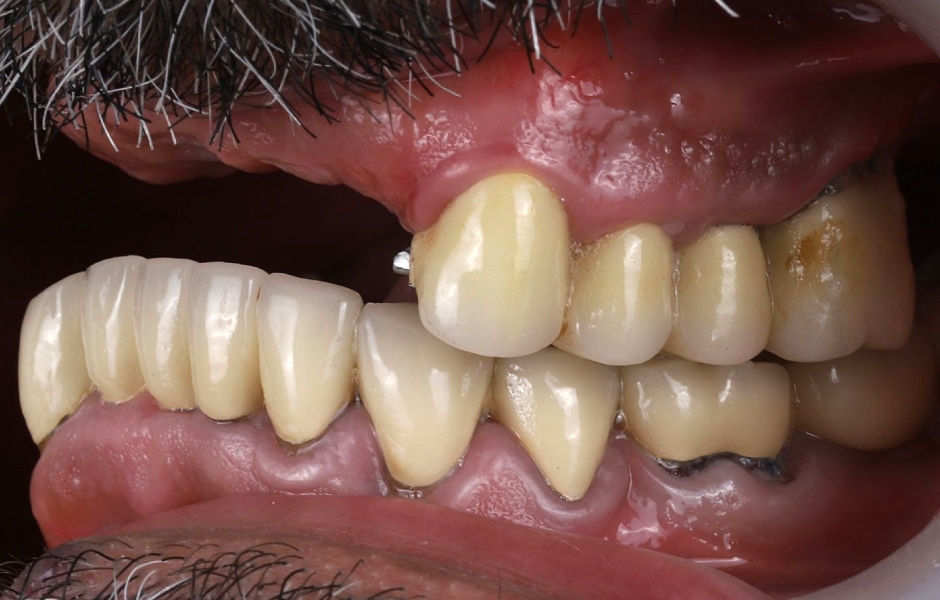

Při extraorální prohlídce nebyly zjištěny žádné významné abnormality. Pacient měl střední úroveň linie úsměvu (obr. 1–3). Po vyjmutí snímatelné náhrady byl odhalen můstek (obr. 4).

Intraorální vyšetření odhalilo starý můstek, který nahrazoval zuby 23 až 26 a zároveň sloužil ke kotvení částečné snímatelné náhrady s kovovou výztuží. Zuby 22 až 17 byly extrahovány již před delší dobou a alveolární hřeben v této oblasti byl zhojen. Nebyl přítomen plak ani zánět. Zuby vykazovaly mírnou až střední ztrátu attachmentu, ale nebyly pozorovány žádné parodontální léze nebo fraktury kořenů (obr. 5–8).

Obr. 3, 4

Obr. 5

Obr. 6

Obr. 7

Obr. 8